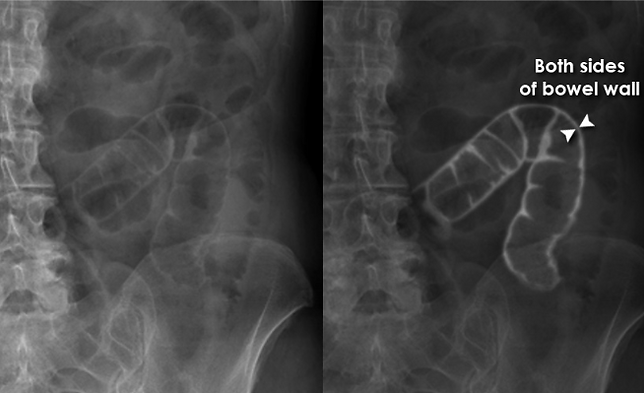

Where it shouldn’t be: free intraperitoneal air—look for the Rigler sign (double bowel wall on supine view) or subdiaphragmatic air on erect/decubitus. Treat as perforation until proven otherwise.1,3,4